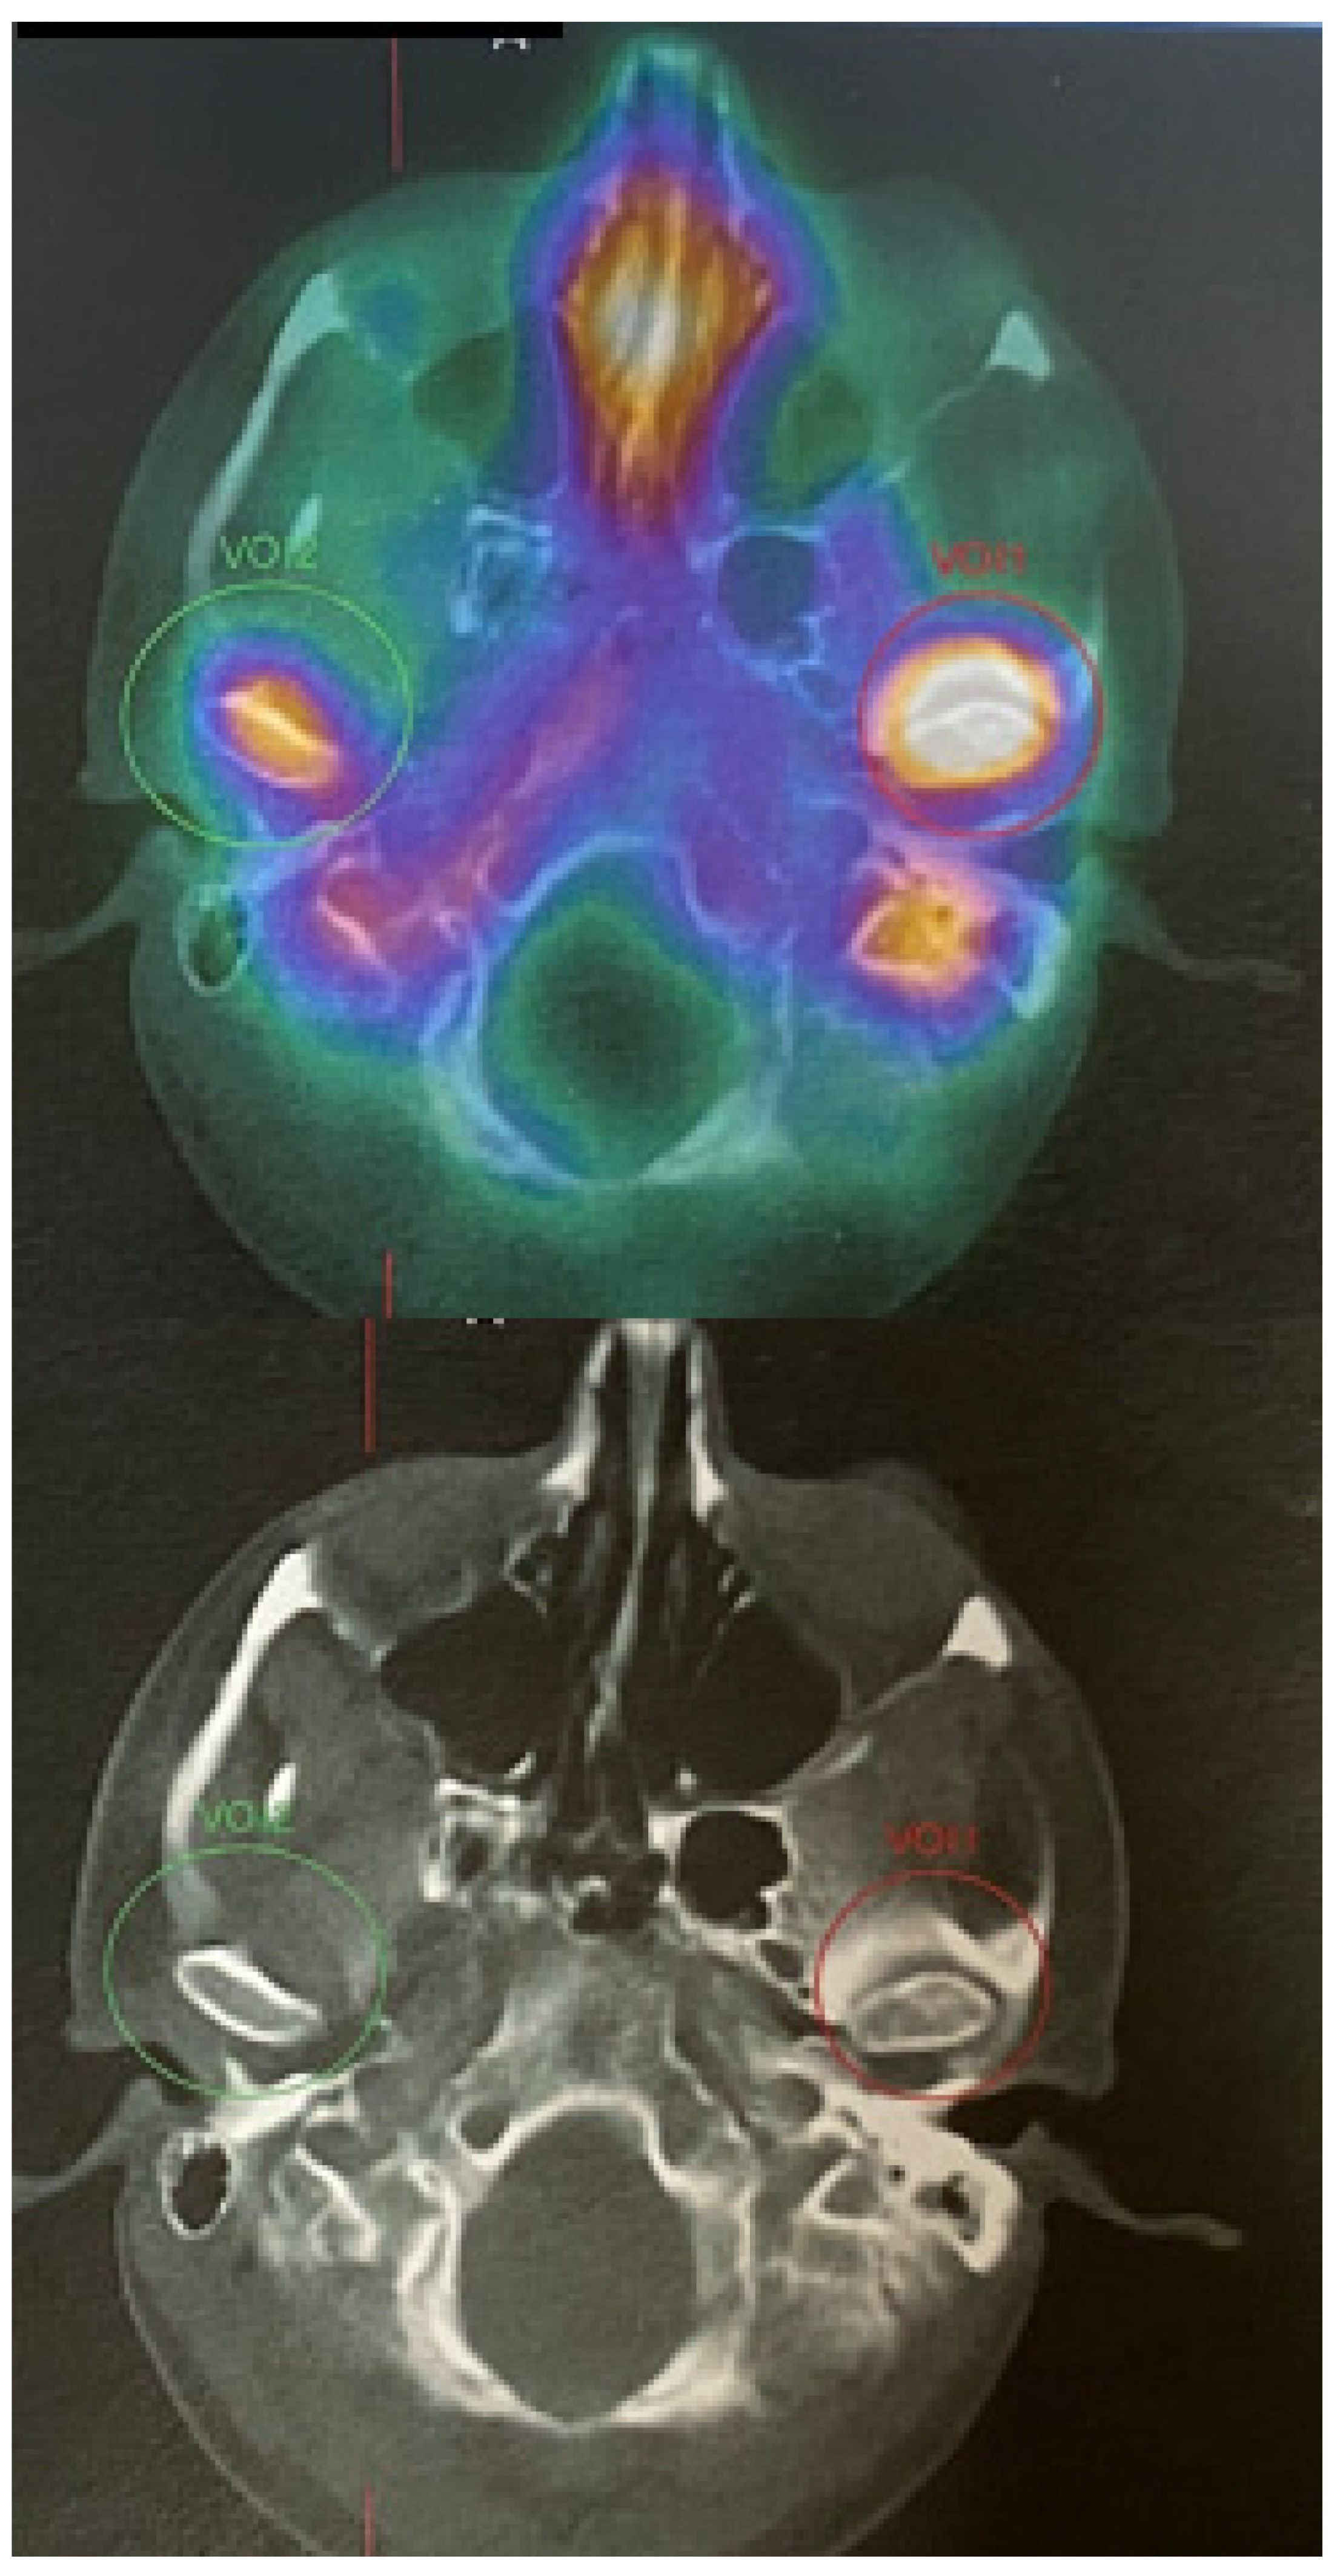

Figure 4.

SPECT-CT of the facial skeleton revealed an atypical, extensive, and progressive accumulation of growth in the left mandibular condyle head. The MDP Tc99m (Technetium 99m methylene diphosphonate) is quite important because any accumulation within the affected condyle might either mean inflammation, bone growth, abnormal bone growth, bone tumor, joint overload, some atypical tumors/bone metaplasia, or other findings when the craniofacial skeleton is evaluated. Some authors suggest that the differences in radio uptake of more than 10–15% might suggest growing condylar hyperplasia; however, a full clinical, radiological and SPECT comparison should be drawn at least two times in 4–6 months’ time to compare their features. SPECT-CT alone is not enough to confirm any UCH pathology; therefore, a detailed CT/CBCT/LDCT evaluation and clinical patient examination can greatly influence the future final identification of the disease. Many authors emphasize that SPECT is a very important diagnostic tool and should be always performed in cases of any skeletal asymmetries, especially mandibular asymmetry [4,5]. Abbreviations: UCH—unilateral condylar hyperplasia; CT/LDCT—computed tomography/low-dose computed tomography; green circle–negative growth; red circle–proggresive bone growth in SPECT.